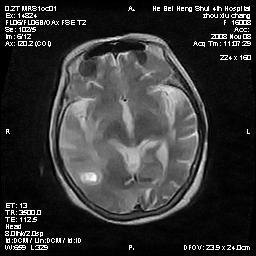

标题: MRI1883:女67岁,半年前曾患脑梗塞,治疗后好转,近3各月精 [打印本页]

女67岁,半年前曾患脑梗塞,治疗后好转,近3各月精神恍惚。

两种可能:1,转移瘤,2,脑炎,建议增强扫描

形态及整体病灶看起来首先考虑转移瘤或淋巴瘤,但奇怪的是多个病灶周围均未见显著的水肿区,这不符合这两个肿瘤的特点,结合ct表现及患者病史有个人考虑是否有皮层下动脉硬化性脑病伴多发胶质增生可能.

不像占位性病变,考虑脱髓鞘改变

皮层下动脉硬化性脑病伴脱髓鞘改变!